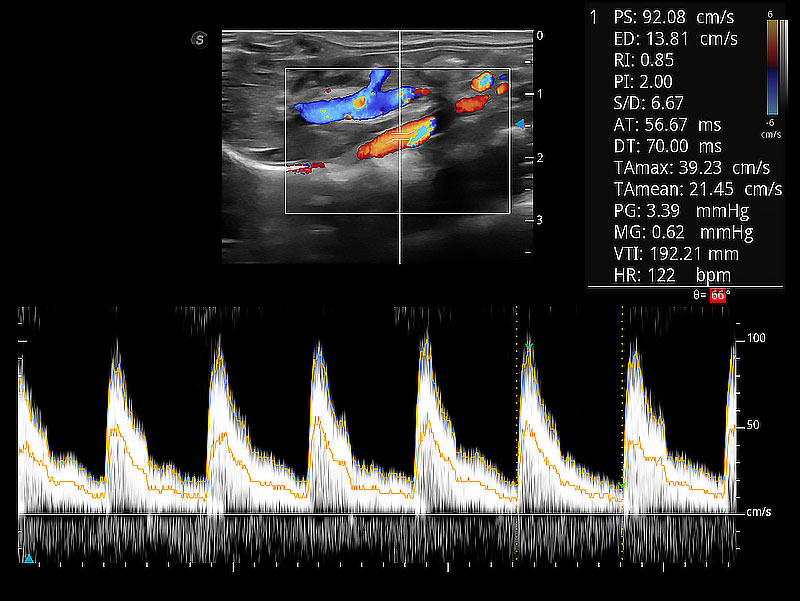

随着取样门位置改变,频谱多普勒包络可进行自动眼踪测量,且可自由配置测量的参数。